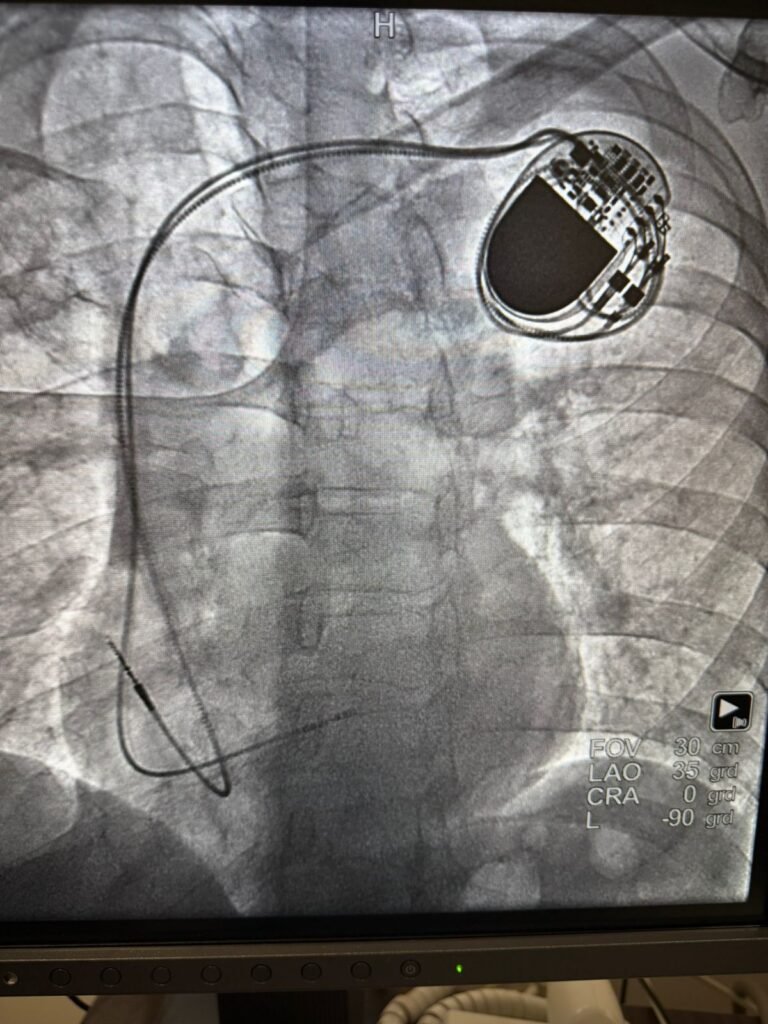

● En el marco de estas actividades, realizadas el 24 y 25 de marzo, se colocaron tres marcapasos a pacientes de 44, 59 y 65 años, y se llevaron a cabo dos cateterismos diagnósticos a derechohabientes de 77 y 38 años, uno de ellos referido al Hospital Regional de Alta Especialidad “Centenario de la Revolución Mexicana” del ISSSTE en Morelos para recibir tratamientos propios de un tercer nivel de atención

Durante la jornada, realizada el 24 y 25 de marzo, se colocaron tres marcapasos a pacientes de 44, 59 y 65 años, quienes presentaban síntomas como mareos y taquicardia.

Además, los especialistas Gerardo Rodríguez Diez y Alejandro Alcocer Chauvet, provenientes del Centro Médico Nacional (CMN) “20 de Noviembre” y el Hospital Regional (HR) “1° de Octubre” de la Ciudad de México, colocaron a un paciente de 49 años con diabetes e hipertensión, un stent o malla metálica para normalizar el flujo sanguíneo que va hacia su corazón.

Los tratamientos se llevaron a cabo en la sala de hemodinamia de esta unidad médica, equipada con equipo especializado de última generación, como un fluoroscopio y una pantalla que permite observar imágenes en tiempo real en formato tridimensional.